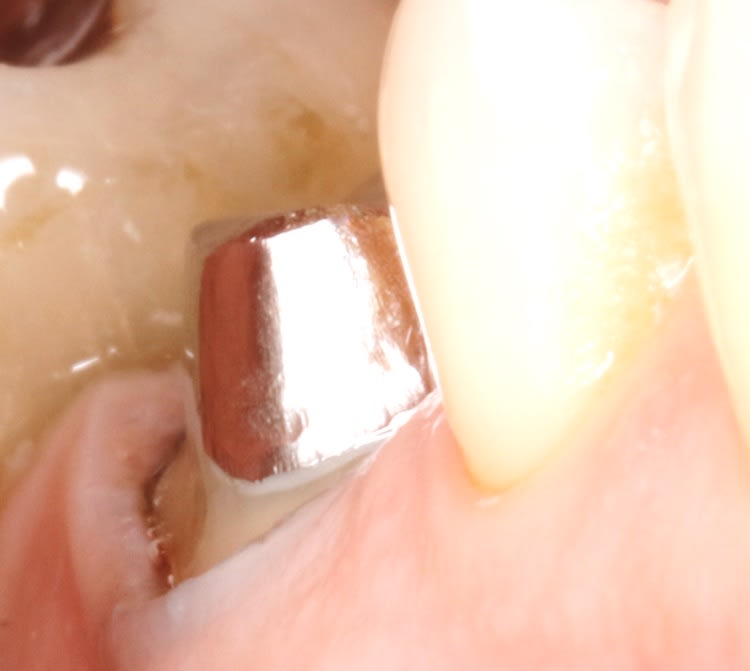

et là ç est le 1 er jour , le jour de l endo .

le but est de pretailler la dent en restant juxta .

en aucun cas ,il faut toucher la gencive le 1 ere séance . ( sauf s'il y a carie bien sur , mais ç est tres ponctuel ).

la seance d apres , alors que l on a pas touché la gencive , hein , et bien elle va se rétracter , pcq elle sera stimulée mecaniquement .

de plus si la dent bouge , elle egressera 1 poil ,et ne bougera plus . ça ç est impressionnant aussi .